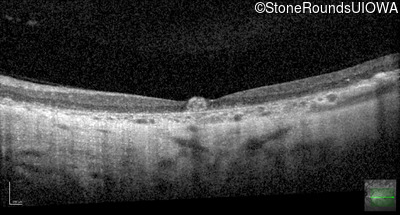

Optical Coherence Tomography - Right - 20/63

Exemplar / OCT Stack